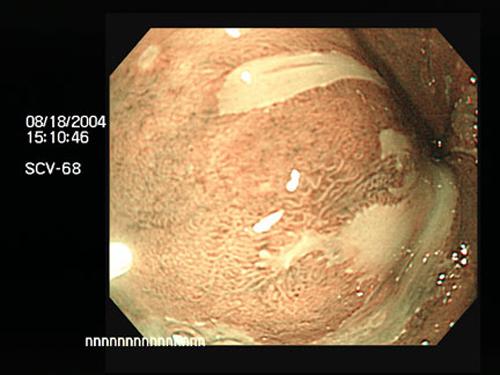

Narrowband imaging (NBI) improves detection and delineation of certain lesions in Barretts esophagus by enhancing their abnormal surface and small vessel pattern relative to standard whitelight endoscopy. Courtesy Mayo.edu